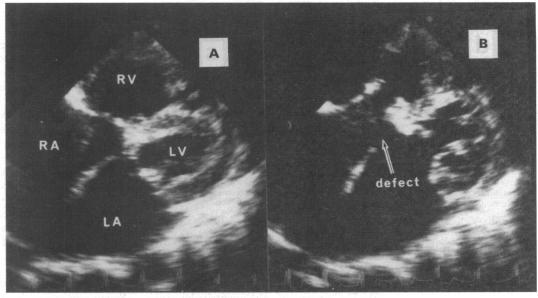

135 patients with typical AVSD and with nine patients with atypical AVSD, characterised by a well formed atrial septum, a milder downward displacement of the atrioventricular valves, and a shorter length of the ostium primum defect.

All nine patients with atypical AVSD had an unusual mean frontal QRS axis compared with six of the 135 patients (4%) with typical AVSD (p < 0.01). All eight patients who underwent the vector analyses showed atypical movement of the QRS loop--that is, an initial left inferior movement in the frontal loop (eight patients) and counter-clockwise rotation in the sagittal loop (seven). The corresponding values for 119 patients with typical AVSD were 20 and 22 patients (p < 0.01). Seven patients with atypical AVSD (78%) and 55 (41%) with typical AVSD had Down's syndrome (p < 0.05). None of the twenty one patients with additional cardiac anomalies had atypical AVSD, an unusual QRS axis, or unusual movement in the QRS loop.

135例典型AVSD患者和9例非典型AVSD患者,其特征为房间隔形成良好、房室瓣向下移位较轻以及原发孔缺损长度较短。

与135例典型AVSD患者中的6例(4%)相比,所有9例非典型AVSD患者的平均额面QRS轴均异常(p<0.01)。所有8例行向量分析的患者均显示QRS环运动异常,即额面环初始向左下运动(8例),矢状环逆时针旋转(7例)。119例典型AVSD患者的相应数值分别为20例和22例(p<0.01)。7例非典型AVSD患者(78%)和55例典型AVSD患者(41%)患有唐氏综合征(p<0.05)。21例合并其他心脏异常的患者中,无一例患有非典型AVSD、异常QRS轴或QRS环运动异常。